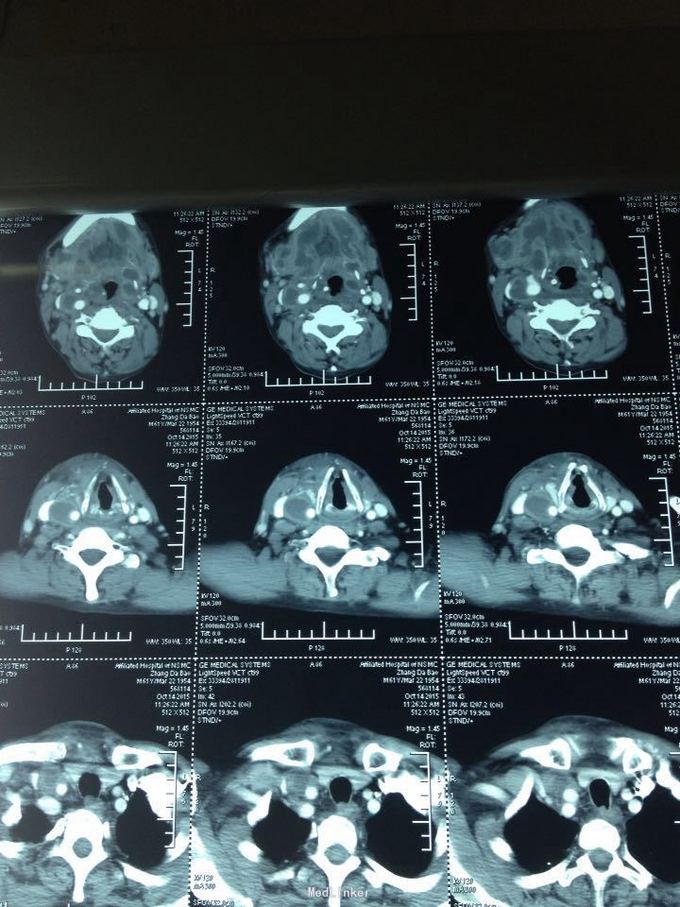

颈部肿痛10多天。10多天前无明显诱因出现颈部及颌下疼痛,肿胀明显,吞咽受限,无伴明显呼吸困难。无高热、寒战等。未特殊处理,上述症状渐加重。

双侧颈部肿胀明显,皮肤稍充血,皮温较高,可触及波动感,压痛明显,右侧为甚,咽部黏膜充血肿胀明显。

颈部多发脓肿。入院后完善相关检查,给予抗感染、对症支持治疗,并于急诊全麻下行颈部脓肿切开引流术,术中分离右侧颈动脉鞘,充分分离脓腔,充分引流。

颈部感染致脓肿多发是颈部感染的严重转归,而脓肿累及颈鞘时需要高度警惕,防止脓液腐蚀动脉血管,导致血管破溃大出血而致患者休克甚至死亡,需要充分告知患者及家属具体风险,手术中需要尽可能彻底分离脓腔,动脉周围脓肿需要谨慎分离。注意保护。